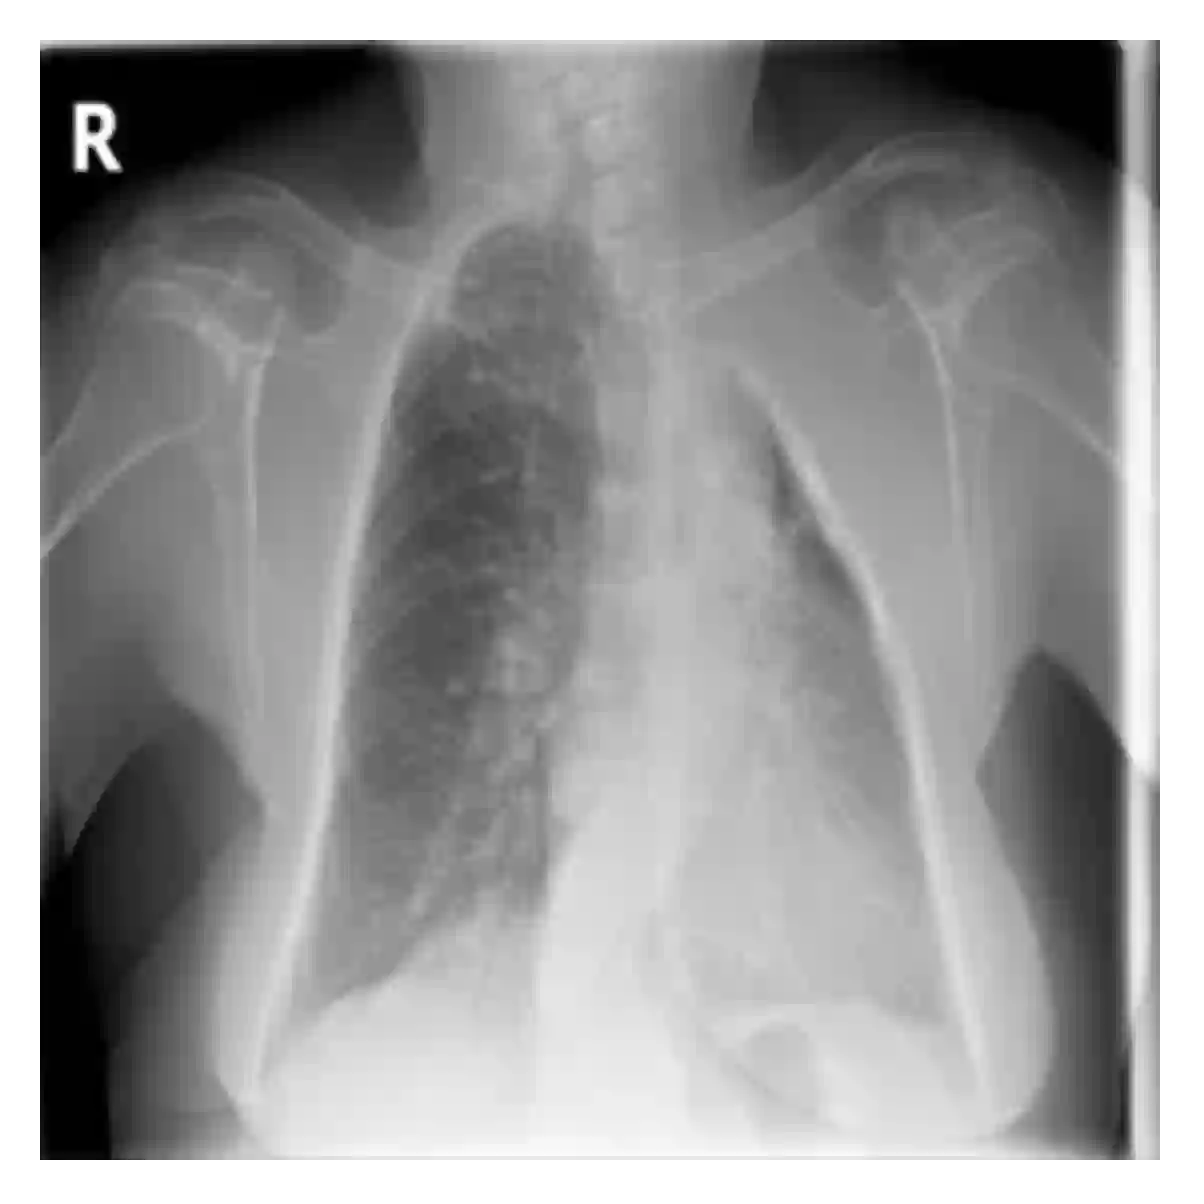

The evaluation of infectious disease processes on radiologic images is an important and challenging task in medical image analysis. Pulmonary infections can often be best imaged and evaluated through computed tomography (CT) scans, which are often not available in low-resource environments and difficult to obtain for critically ill patients. On the other hand, X-ray, a different type of imaging procedure, is inexpensive, often available at the bedside and more widely available, but offers a simpler, two dimensional image. We show that by relying on a model that learns to generate CT images from X-rays synthetically, we can improve the automatic disease classification accuracy and provide clinicians with a different look at the pulmonary disease process. Specifically, we investigate Tuberculosis (TB), a deadly bacterial infectious disease that predominantly affects the lungs, but also other organ systems. We show that relying on synthetically generated CT improves TB identification by 7.50% and distinguishes TB properties up to 12.16% better than the X-ray baseline.